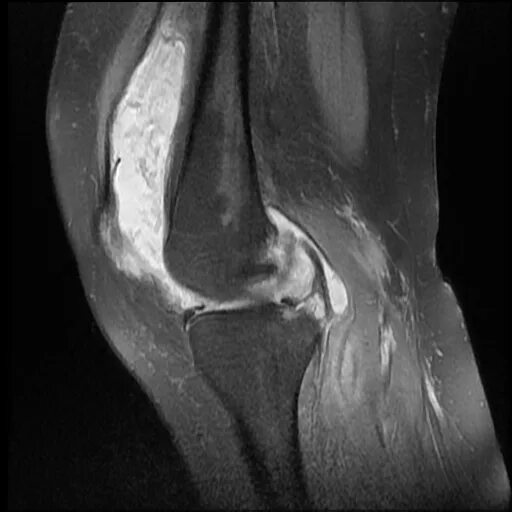

Что такое синовит коленного сустава на мрт